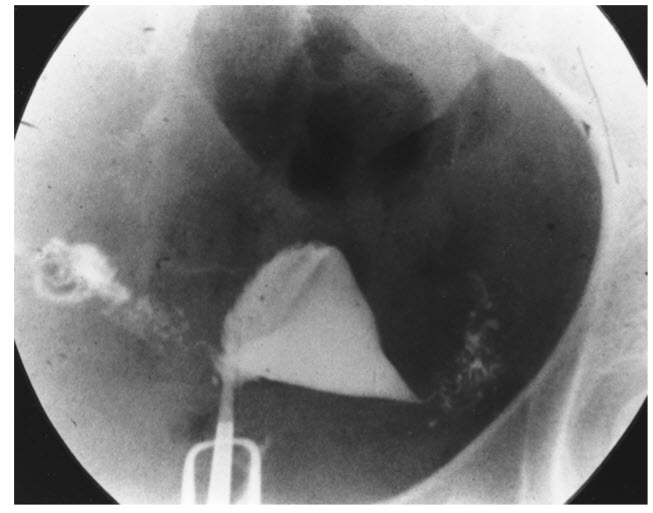

Hysterosalpingography is an important tool in the evaluation of infertility. It provides information regarding the shape of the uterine cavity and the patency of the tubes. Tubal factors, which may result from sexually transmitted diseases, are an important cause of infertility. The figure shows salpingitis isthmica nodosa, in which there is a characteristic “salt-and-pepper” pattern of tubal filling and evidence of a diverticulum of the tube on one side.